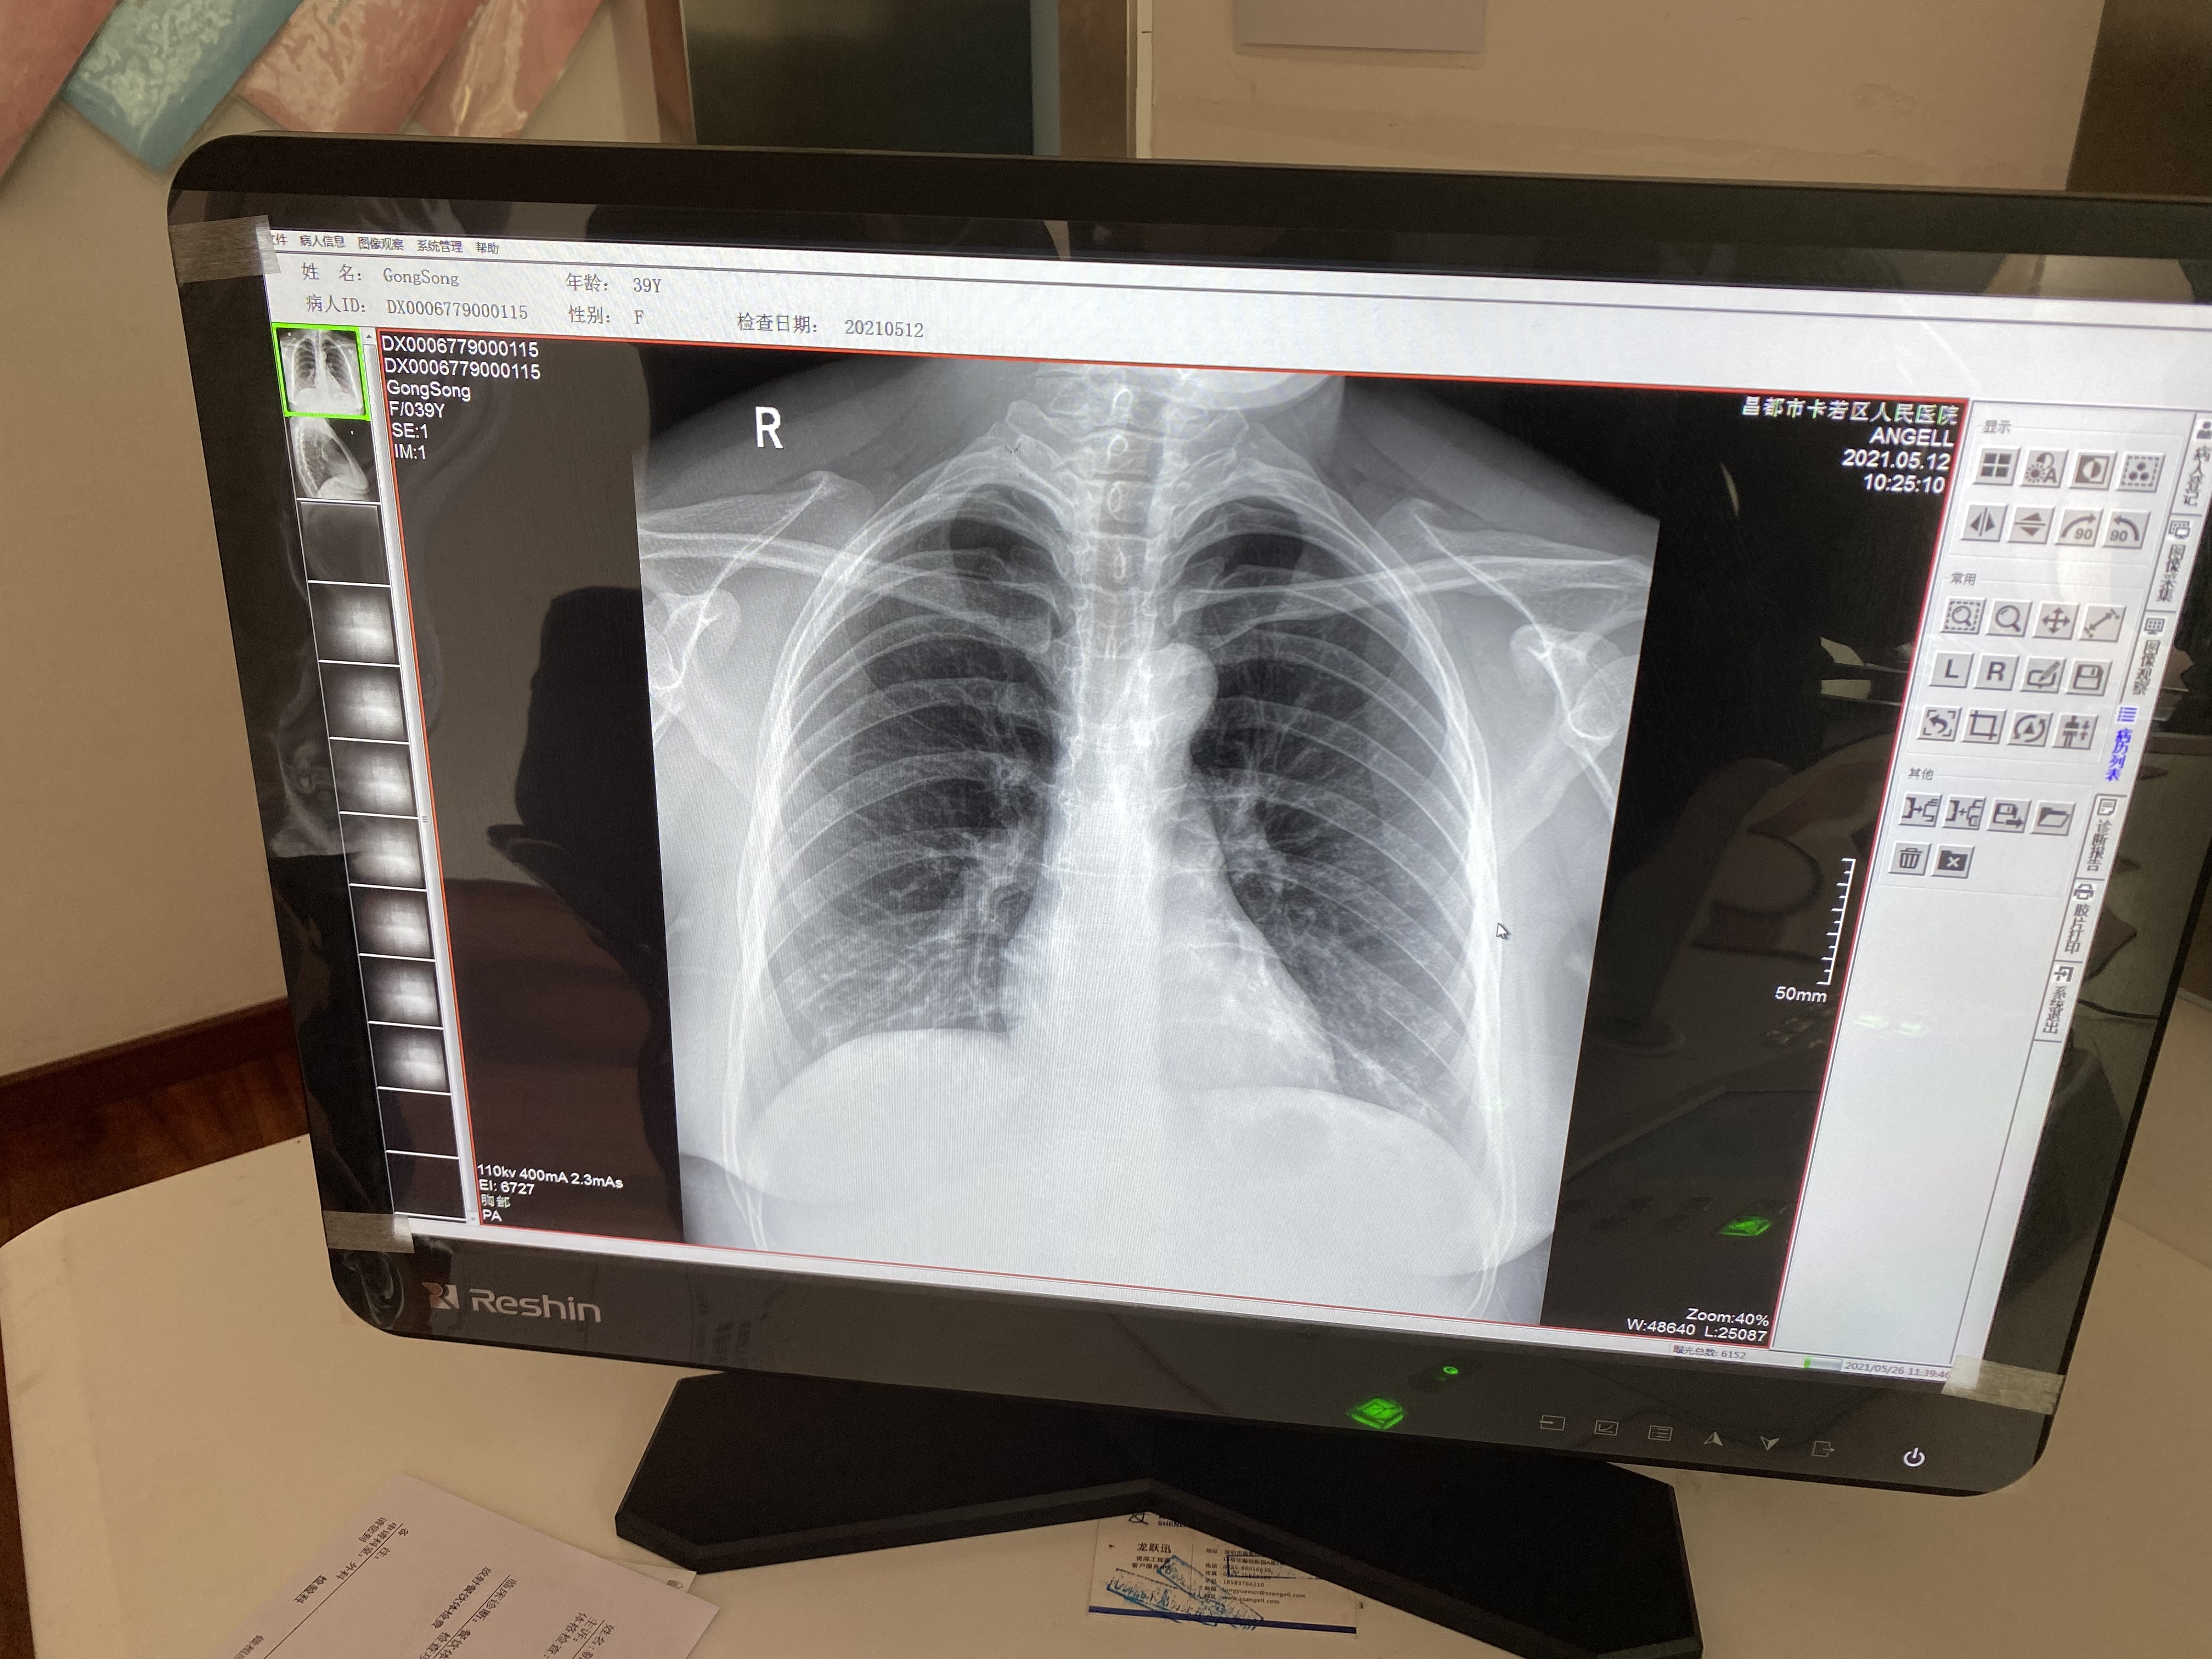

6:騰靈的胸片攝片臨床影像

作為一款動態多功能診斷專用DR設備,騰靈支持高清攝片、透視攝影、造影攝影、全脊柱攝影、全下肢攝影檢查于一身,滿足低人口密度地區的多種數字化X線攝影檢查需求。在卡若區人民醫院,每天大約有60人左右的檢查人次,來自于一區十縣 24個鎮118鄉的藏區百姓,騰靈在過去近一年的服役中贏得了放射科主任及主管技師的一致認可。

“這個設備好得很,現在我們這個醫院就1臺這個設備,每天都在給病人做檢查。摁一下摁扭它就可以立起來,體檢病人的時候我們就立起來檢查,拍出來的圖像很清楚。它也可以橫著放,拍腰椎的病人、骨關節的病人,我們摁一下就可以平放攝片。我們現在已經檢查了差不多有1多萬個病人了,機器沒有出現什么問題,工程師也會經常詢問設備的情況,這個設備美得很。”操作設備的主管技師說。

目前,卡若區人民醫院放射科僅有3名技術與診斷醫師,都是昌都本地的藏族年輕人,沒有像內地城市的二甲醫院放射科進行技術與診斷的分組,在卡若技師也是診斷醫師。技師每天既要完成擺位、攝片,同時也要完成閱片與診斷報告的書寫,承受著艱巨的檢查任務與診斷壓力,確保讓每一位患者都能得到精準的檢查保障。這種情況,在藏區也是普遍的現象,缺少醫師是目前藏區醫療服務能力建設中比較急迫的問題。